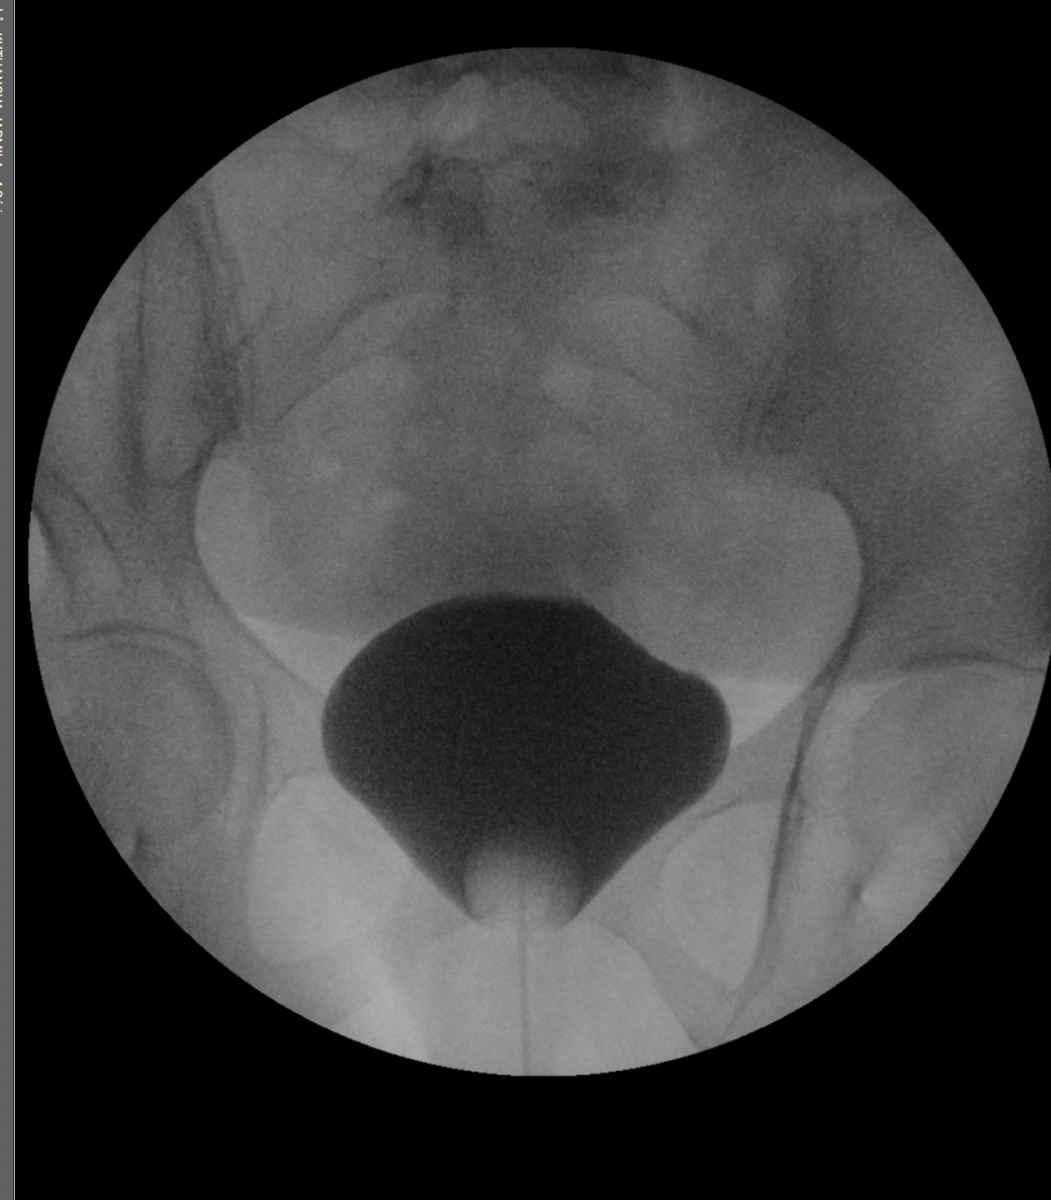

Vyšetření močové trubice a močového měchýře – cystografie a uretrografie

Tato vyšetření slouží k diagnostice onemocnění močové trubice a močového měchýře – nejčastěji zúžení močové trubice. U dětí se vyšetření provádí k vyloučení vezikoureterálního refluxu.

Vyšetření provádíme ve spolupráci s urologem, popřípadě dětským lékařem.

Kontrastní látka je hadičkou (s cévkou) aplikována do močového měchýře či močové trubice. Po naplnění močového měchýře se zpravidla pacient vymočí v RTG kontroly.

Doba vyšetření asi 30 minut.

Příprava před vyšetřením není nutná.